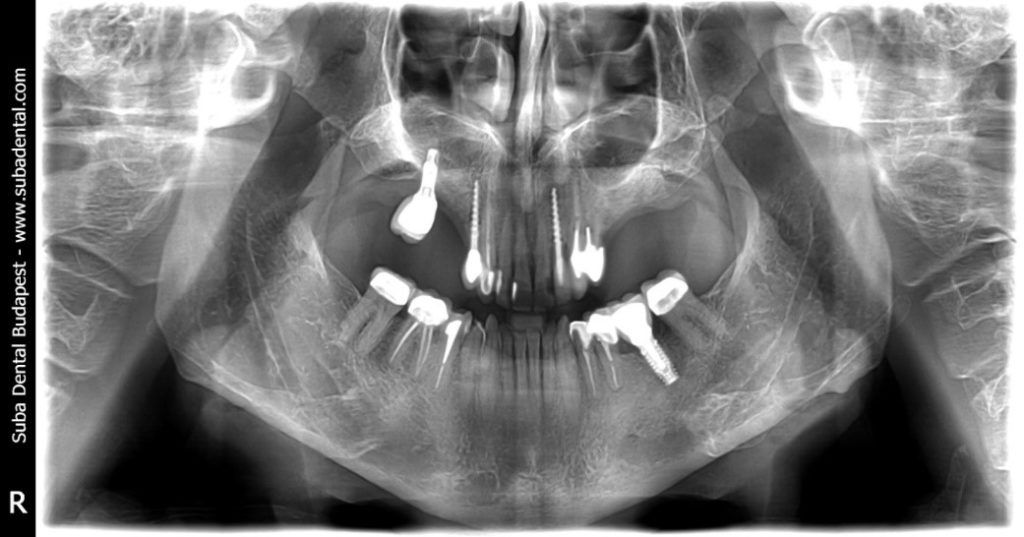

Panorámaröntgen-felvétel a kiinduló helyzetről

Az első találkozó alkalmával CBCT (Cone beam computed tomography) felvétel készült, hogy a csontkínálatot 3 dimenzióban tudjuk vizsgálni az implantálás előtt. A CT felvétel alapján kiderült, hogy a bal oldalon az őrlők helyén nem megfelelő a csontmagasság, és csontpótlásra, úgynevezett sinus liftre lesz szükség. A jobb oldalon a korábbi foghúzás helye nem jól gyógyult, és egy sebészi tisztításra, kaparásra lesz szükség, hogy a benőtt lágyszöveteket (granulációs szövet) eltávolítsuk. A 17-es fog helyén lévő implantátum, melyet korábban egy másik klinikán kapott, szintén nagyon rossz állapotban volt, és a körülötte lévő nagyfokú csontfelszívódás és gyulladás, periimplantitis indokolttá tette a régi implantátum eltávolítását (explantáció).